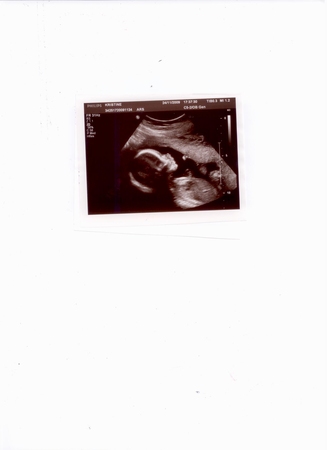

А вот моя младшенькая красавица: